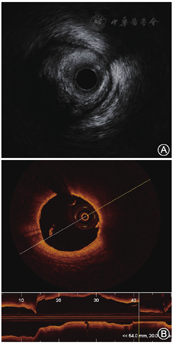

OCT具有更高的分辨率,OCT定义TCFA是薄纤维帽粥样斑块,即富含脂质的斑块,脂质角度≥ 90°,纤维帽厚度<65 μm的斑块。TCFA在冠状动脉分布上表现出近端聚集现象,且在急性冠状动脉综合征(acute coronary syndrome,ACS)患者的左前降支(left anterior descending,LAD)中尤为明显;纤维斑块分布则相对均匀[7](图1)。TCFA是易损斑块的典型代表,与无复流现象相关,无复流发生率随着罪犯病变脂质角度的增大而增加。OCT评估的MLA<3.5 mm2、纤维帽厚度<65 μm、脂质核心角度>180°及巨噬细胞浸润均与12个月冠状动脉事件风险增加相关[8]。OCT提示的MLA<3.5 mm2的TCFA病变与4年随访时的心源性死亡、心肌梗死和再次PCI明显相关[9]。

IVUS和OCT简要操作流程如图4所示(具体操作见视频,扫描正文文末二维码观看)。